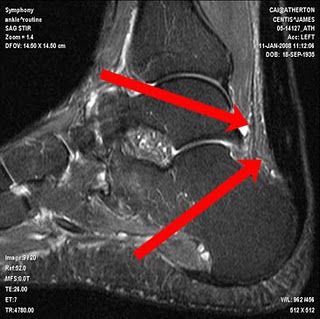

Previous ImageNext Image achilles tendon treatment Share this: Share on X (Opens in new window) X Share on Facebook (Opens in new window) Facebook Share on Tumblr (Opens in new window) Tumblr Email a link to a friend (Opens in new window) Email Print (Opens in new window) Print Like Loading...